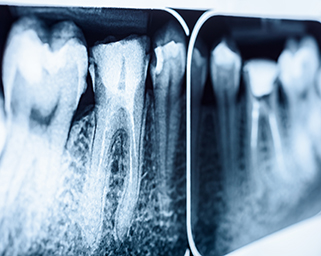

Root Canal Treatment vs Extraction – Why Saving Teeth Matters

When Is a Tooth Extraction Necessary?

Implant v RCT